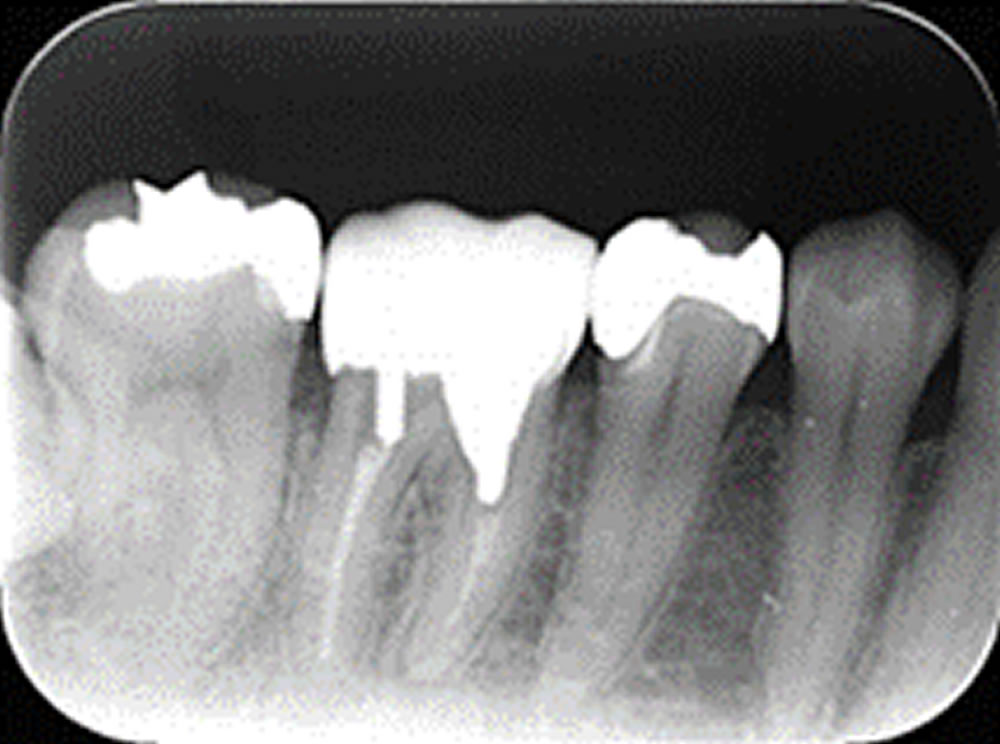

虫歯治療後にセラミックインレーで修復した症例

虫歯治療後にセラミックインレーで修復した症例 こちらの患者さまは、定期検診のレントゲンにて左上7番目の歯にむし歯が見つかりました。 むし歯が大きかったため、しっかりとむし歯を取り除き、セラミックインレーをいれることになり […]